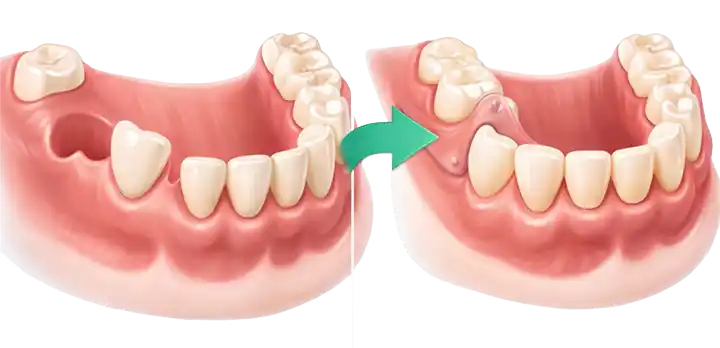

پروتز پارسیل متحرک راهکاری مناسب برای افرادی است که بخشی از دندانهای خود را از دست دادهاند اما هنوز تعدادی دندان سالم در دهان دارند. این نوع پروتز با تکیه بر دندانهای باقیمانده و لثه، فضای خالی را پر کرده و به بهبود جویدن، تکلم و زیبایی لبخند کمک میکند.

- جلوگیری از جابجایی دندانهای باقیمانده

- بهبود ظاهر لبخند و فرم صورت